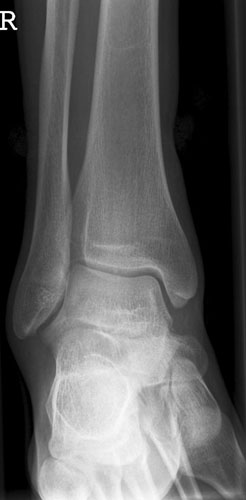

OSG seitlich

132_3.jpg

Fehler

Doppelkonturierung im vorderen Teil der Talusrolle. Die Fibula ist gegen dem Malleolus internus nach ventral verschoben. Die Längsachse des Talus ist verkürzt. Das untere Sprunggelenk kann nicht beurteilt werden.

Abhilfe

Keilkissen unter den Calcaneus legen bzw. Fuß flacher auf den Zehen auflegen lassen.